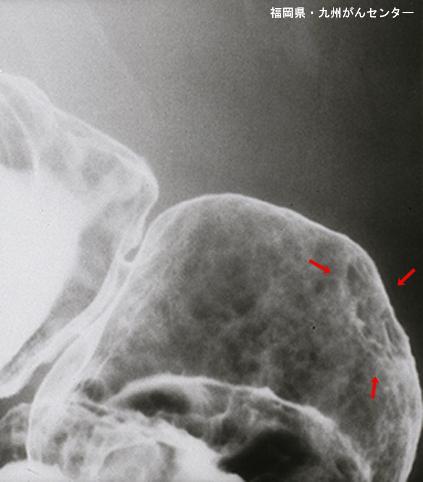

症例提示(所在地,施設名等): 福岡県・ 九州がんセンター

疾患(病理主体)の分類良性上皮性腫瘍/腺腫

部位(臓器別)胃(部位)/前庭

検査方法X-P

腫瘍の肉眼分類0型(表在型)/IIc型(IIc)

病変の最大径(ミリ)10〜14